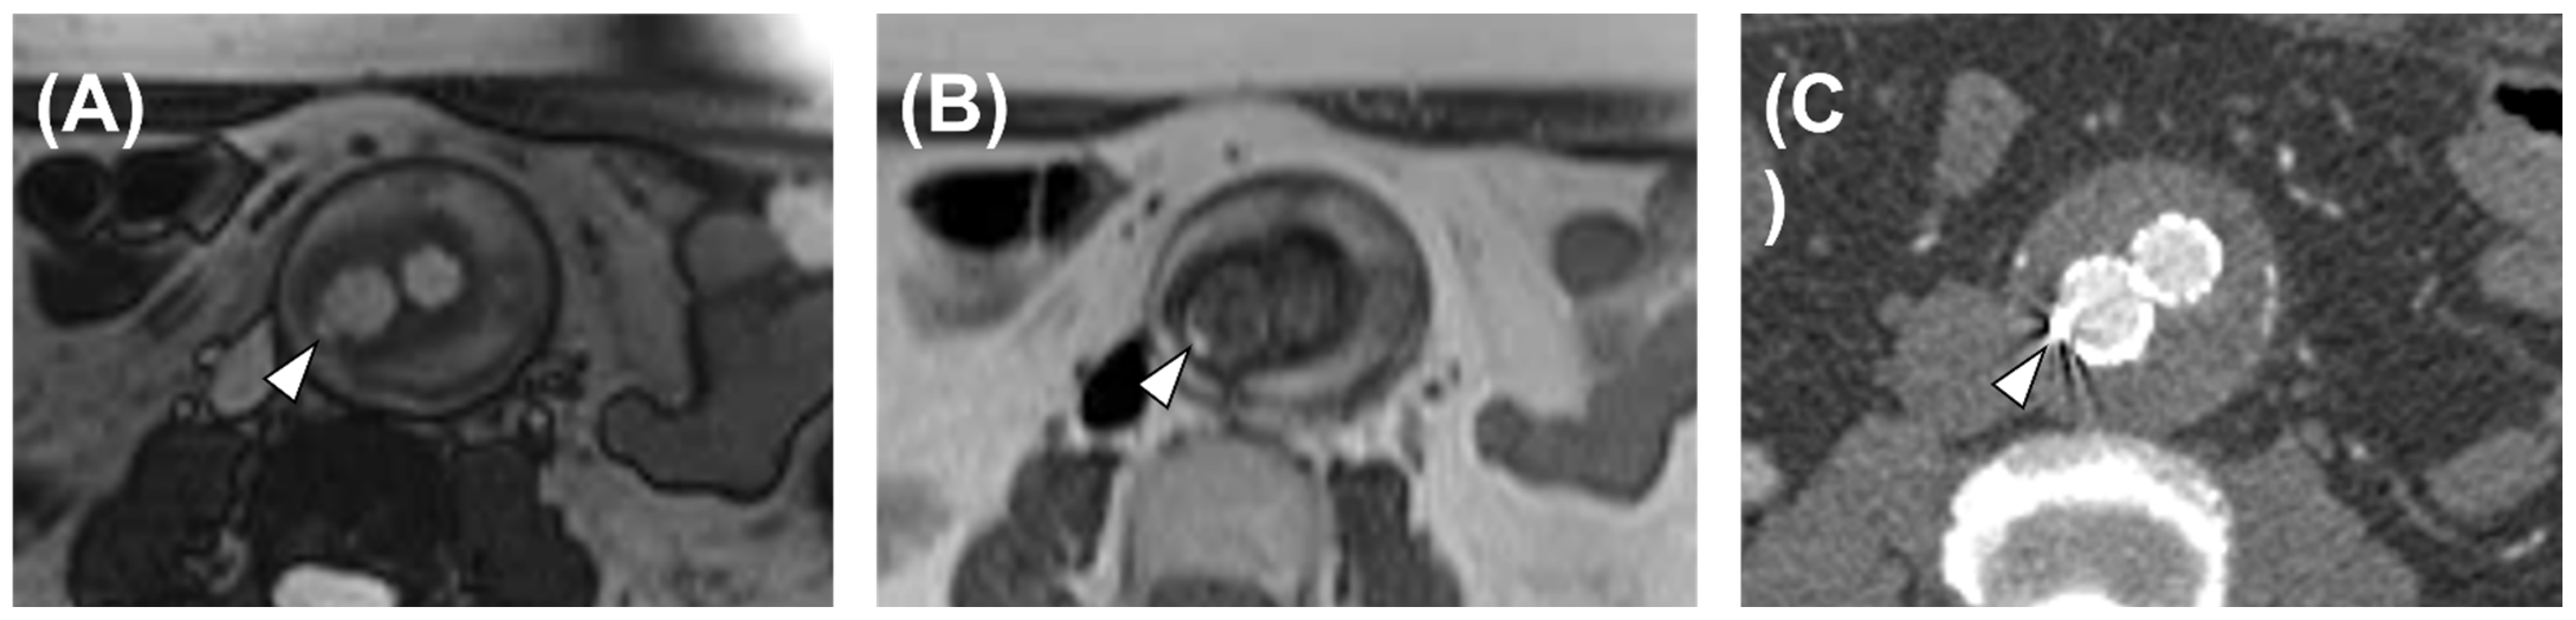

3.2. Morphological MRI Diagnostic Performance

3.3. Flow MRI Diagnostic Performance

4. Discussion